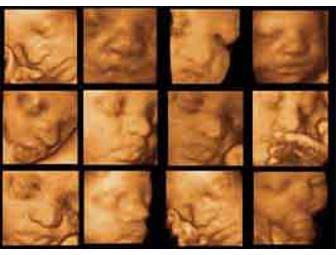

3D Babyface Sonography

See your unborn baby like only today's most sophisticated technology can show. Come to a beautiful practice where more OBGYNs refer. This is an experience you will never forget. A 2D, 3D, 4D ultrasound from Souther California's most respected practice. Includes a high resolution CD/DVD, 8.5 x 11 picture and 40 minutes of viewing time.

3D Babyface Sonography